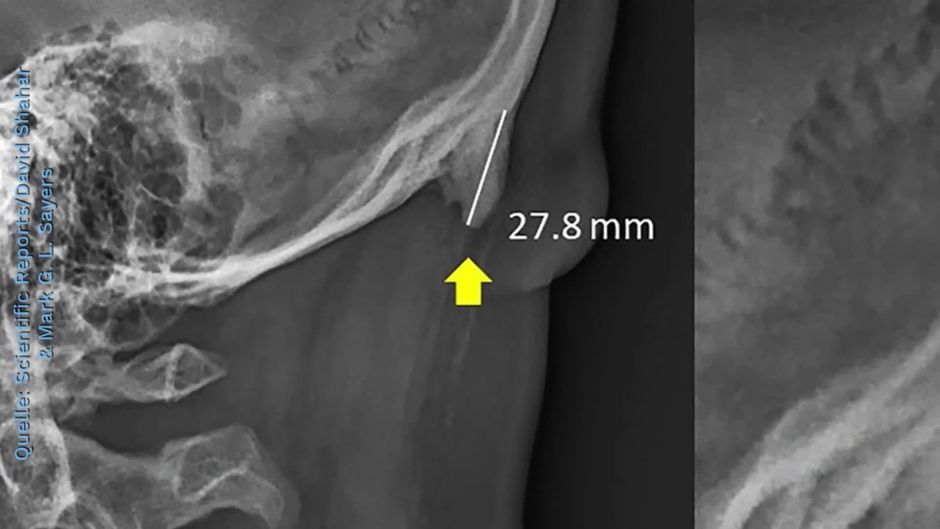

Das Smartphone in der Hand, der Kopf gesenkt - diese Fehlhaltung haben wir uns angewöhnt. Doch offenbar führt das zu einer merkwürdigen Fehlbildung am Hinterkopf. Das zumindest wollen australische Ärzte entdeckt haben.